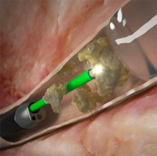

En caso de optar por técnicas endourológicas, estás tienen la ventaja de la escasa morbilidad y recuperación rápida por parte del paciente, ya que se usan instrumentos muy finos para llegar a la o las litiasis y mediante diversas fuentes de energía se consigue fragmentar y/o pulverizarlas. Dentro de las diversas fuentes de energía el láser es la más versátil, ya que se transmite mediante fibras muy pequeñas de diversos calibres, que pueden pasar por los diversos canales de trabajo y acoplarse a instrumentos rígidos y flexibles llegando a localizaciones complejas, lo cual no se puede conseguir con otras fuentes de energía (energía mecánica o ultrasónica), además la energía puede ser modificada para conseguir un mejor efecto sobre la litiasis según su dureza, ya sea fragmentándola y posteriormente retirarla con pequeñas cestas o pulverizarlas para conseguir la expulsión espontánea por parte del paciente. La efectividad del láser ha sido reconocida por diversas sociedades de urología catalogándola como la mejor herramienta para el tratamiento de las litiasis renales.

Esta enfermedad tiene una prevalencia muy baja entre un 5-10%, sin embargo, el impacto que puede producir en los pacientes que la padecen es muy alta, puesto que generalmente implica la extirpación del riñón y uréter afectado. Sin embargo, en casos seleccionados es posible realizar el tratamiento efectivo mediante ablación con láser, evitando la extirpación y la posible insuficiencia renal ocasionada por estos procedimientos tan radicales. Es importante diferenciar este tipo de tumores de aquellos tumores del riñón que de originan en el tejido del mismo, ya que el tumor de vías se origina en el tapizado interior de las vías urinarias altas.